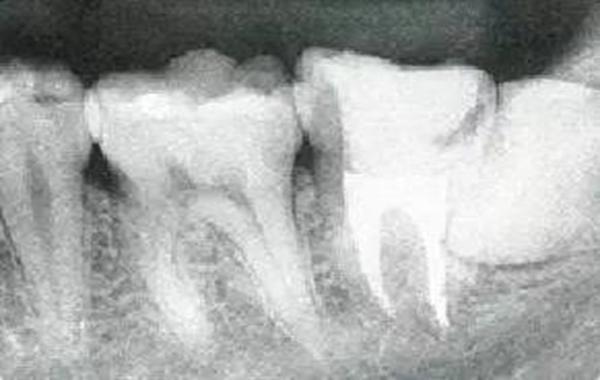

●參考病例① 35歲女性

35歲女性。妊娠4個(gè)月。過(guò)去雖然接受過(guò)刷牙指導(dǎo),但菌斑控制狀態(tài)依然不理想?;颊哂邪l(fā)現(xiàn)自己刷牙時(shí)牙齦出血。

●參考病例② 25歲女性

25歲女性。菌斑控制狀態(tài)不好。齦溝除磨牙處外全在3mm以下,X光照片上左上、右下、左下的第一磨牙上有垂直性骨吸收。這個(gè)病例是參考病例①10年前的狀態(tài),是典型的侵襲性牙周炎局部型。

牙周病的發(fā)展因部位不同而發(fā)展程度不同的。10點(diǎn)后的狀態(tài)參考病例①和參考病例②的磨牙處的狀態(tài)相比較,思考下沒(méi)接受治療病情發(fā)展的特別性吧。

參考病例① 35歲女性

在左下第一磨牙在25歲時(shí)近中處可以看到垂直性的骨吸收,但35歲時(shí)吸收停止,原本沒(méi)有見(jiàn)到的遠(yuǎn)中處骨吸收的,現(xiàn)在卻吸收得很?chē)?yán)重。

在右下處,原本有大量骨吸收的第一磨牙處的吸收卻變緩慢,原本沒(méi)有吸收的第二前磨牙卻出現(xiàn)了吸收。出現(xiàn)吸收的左上第一磨牙的遠(yuǎn)中處,吸收得越來(lái)越多了。